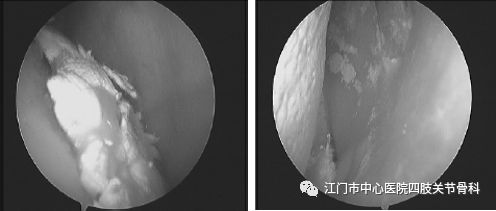

痛风反复发作会引起关节的活动障碍,以膝关节屈曲畸形为多见,关节镜下清理松解+康复训练可以恢复膝关节的活动度,改善生活质量。若痛风长期间歇发作,痛风石沉积会侵蚀关节正常组织,如膝关节半月板、前后交叉韧带、软骨等组织均会被一一侵蚀、吞没,此时想挽救关节也已无力回天,唯有关节置换手术方能恢复关节的功能。